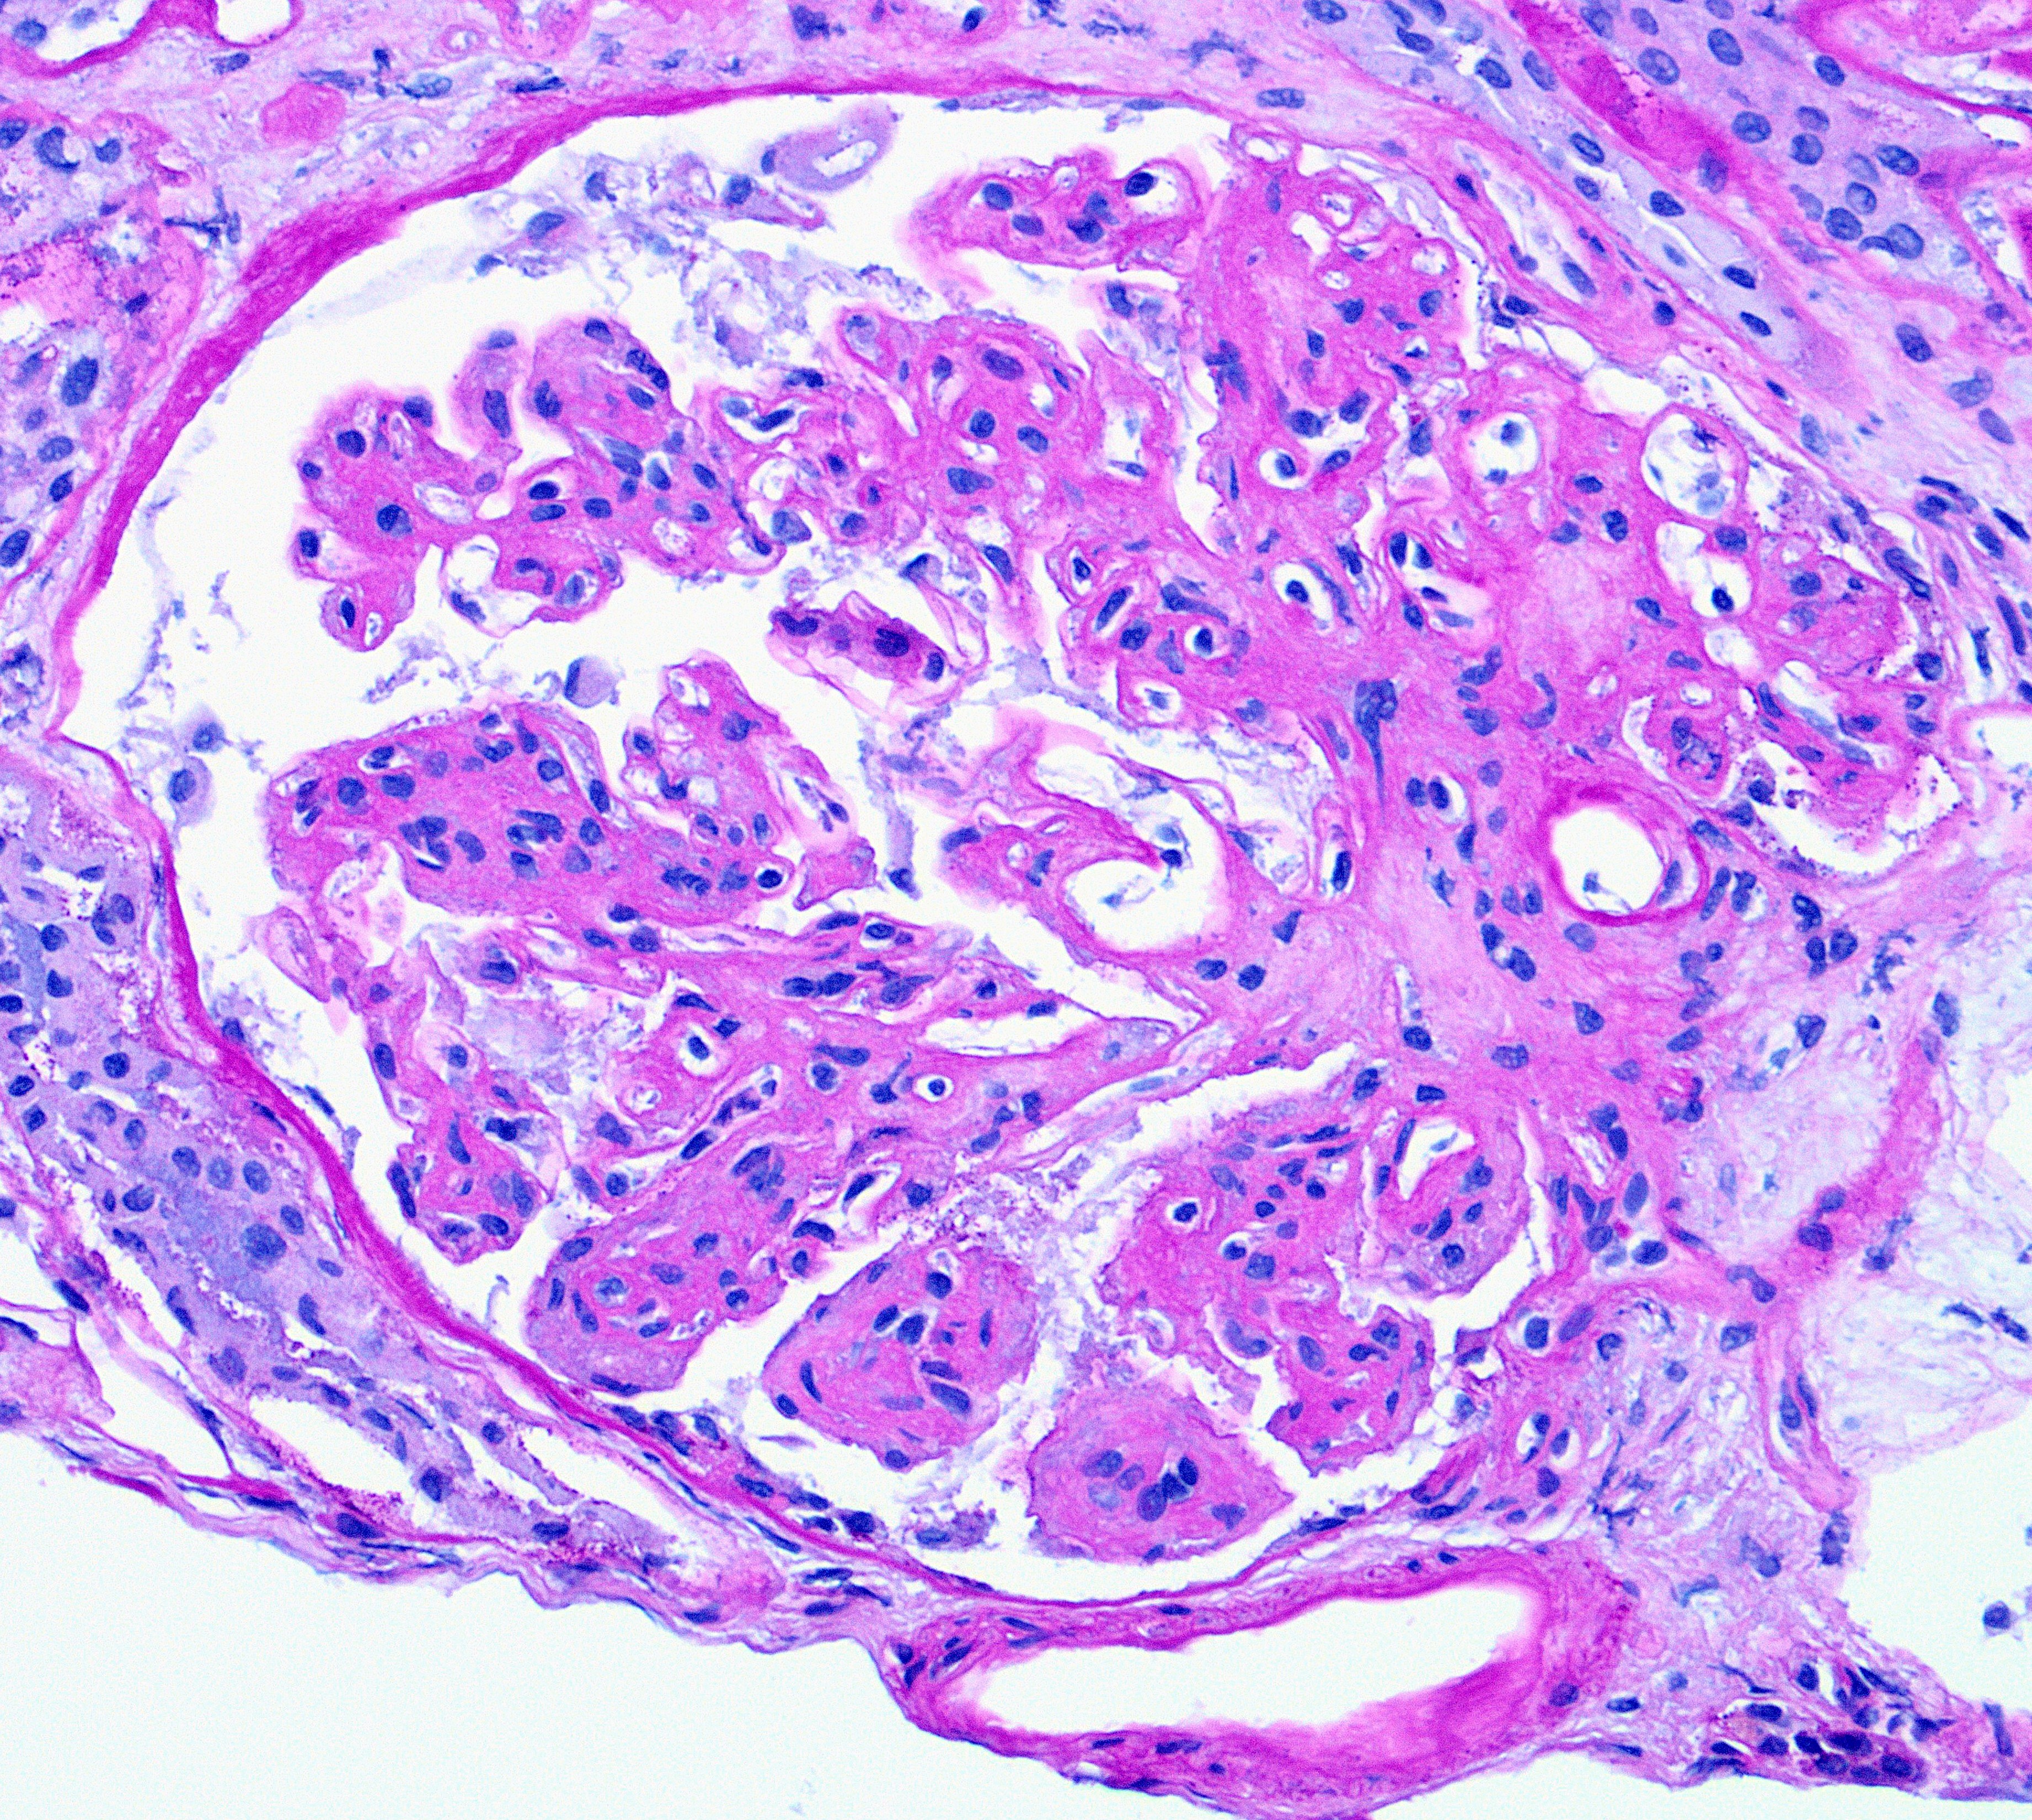

A 79-year old woman with a history of hypertension and colon cancer (1989), s/p sigmoid colectomy, presented with acute renal failure and proteinuria. All serologic workup was negative. IFE showed IgM kappa. Renal biopsy showed membranoproliferative (MPGN) pattern of glomerular injury by light microscopy (H&E Fig a & b). Immunofluorescence was negative. Electron microscopy showed glomerular basement membrane with expanded lamina rara interna and neomembrane formation (Fig c).

The ultrastructural finding of expanded lamina rara interna and neomembrane formation are the result of chronic endothelial cell injury and are c/w chronic thrombotic microangiopathy (TMA), regardless of the etiology. These ultrastructural features causes splitting of the glomerular basement membrane by light microscopy, a feature of MPGN characteristically seen in immune complex mediated diseases. A negative immunofluorescence differentiates chronic endothelial injury (TMA) from immune complex mediated process. Podocyte injury morphologically represents as an extensive foot process effacement, e.g., minimal change disease (MCD). Alport shows splitting and fraying of the lamina densa rather than expansion of lamina rara interna. Finally, resorbed deposits create intramembranous lucent defects, not expansion in lamina rara interna, typically seen in membranous glomerulopathy.